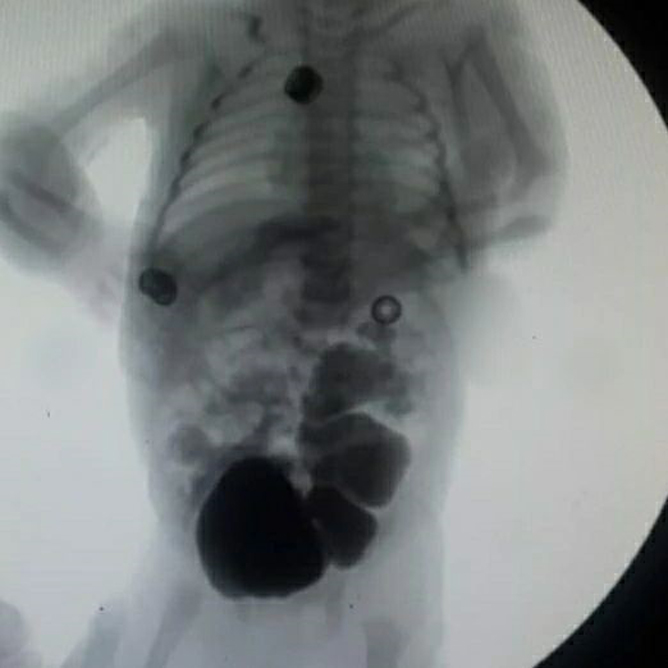

Hələ hamiləliyin 6-cı ayında valideynləri qorxu içərisində bizə müraciət etmişdilər. Hələ anasını bətnində olandan sidiyə çətinliklə çıxırdı, sidik kisəsinin ölçüləri olduqca böyük idi, dölyanı maye azalırdı, hər iki böyrəyində və sidik axarlarında ciddi genişlənmə mövcud idi

Dünyaya gəldiyi gündən də sidiyə çıxa bilmədi, məcburi sidik kateter taxıldı və sonra doğulduğu klinikadan bizim klinikaya gətirildi.

- Sidiyə çətin çıxmasının səbəbi sidik kisəsinin çıxışında olan pərdə posterior uretral valve idi.

- Üstəlik də sidik hər iki sidik axarından böyrəklərə geri qayıdırdı. (Bilateral grade 5 Vezikoüreteral reflüks)

- Belə vəziyyətdə gözləmək hər iki böyrəyin itirilməsi demək idi...

- Ona görə də məcburi cərrahi əməliyyat qərarı verildi.

- Kamera ilə sidik kanalından girilərək sidiyin axmasına mane olan pərdə kəsildi (PUV ablasiyası)

- Sidik rahat boşalsın deyə sidik kisəsi müvəqqəti qarnın ön divarına kiçik dəlik şəklində birləşdirildi(Vezikostomiya+Sünnət)